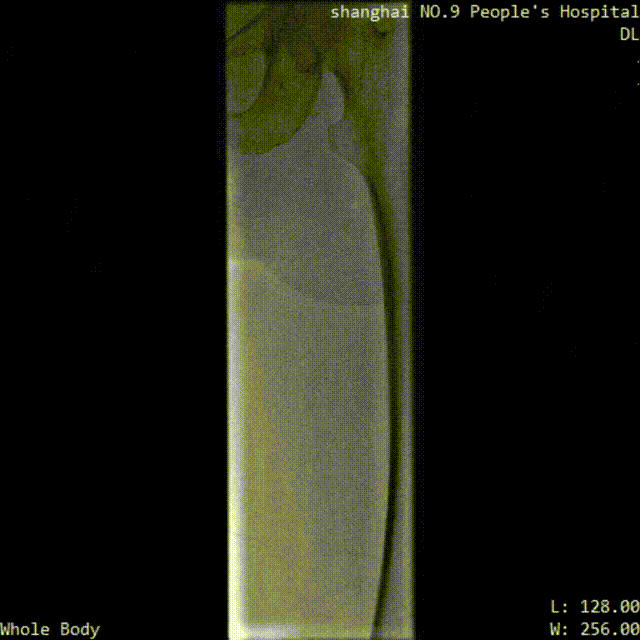

■ LuVoCaptor取栓前后管腔造影对照:

取栓术前管腔造影

取栓术后管腔造影

患者仰卧位,穿刺膝右侧股总静脉,造影定位下腔静脉,肾静脉位置,穿刺腘静脉,放置可回收腔静脉滤器;穿刺左侧腘静脉,置入导鞘,使用LuVoCaptor取栓导管作用靶病变,实施取栓后,造影检查示血栓清除率>90%,取栓后靶血管残余狭窄50%。导丝导管配合通过左髂静脉狭窄闭塞段返回真腔,后行球囊扩张术,再植入Wallstent支架。再次造影见左股浅静脉、股静脉、髂静脉、腔静脉、滤器内连续显影,未见明显充盈缺损,管壁形态血流速度快,造影剂无外渗。支架植入后靶病变狭窄10%。